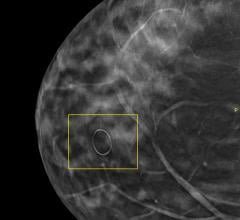

Hitachi Aloka Medical America Inc. and iVu Imaging Corp. announced the signing of an agreement making HAMA the exclusive North American distributor of iVu’s Sofia system, an automated whole breast ultrasound scanner designed for women with mammographically dense breasts.

Despite decades of progress in breast imaging, one challenge continues to test even the most skilled radiologists ...